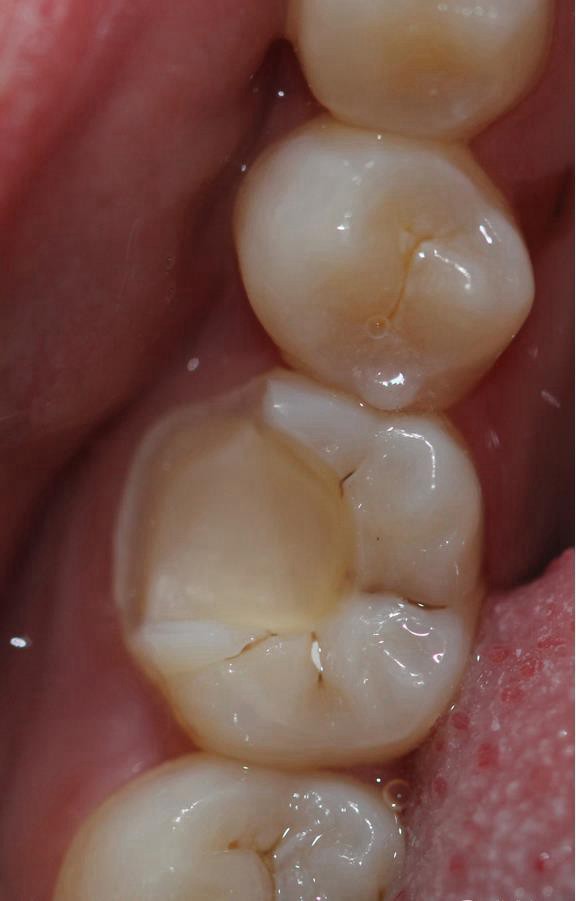

根管治療完之后,樹(shù)脂墊底,不需要加樁 不管你是做樹(shù)脂嵌體還是瓷嵌體。

牙體根充完制備 ,剩余的牙體組織最小的厚度為2mm。